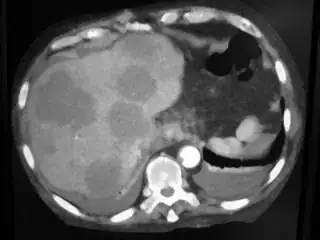

Below I apply two successive morphological openings to the image using a 3x3 circular kernel, and then apply k-means clustering to the gray levels. From your sample images and some I found on the internet, I decided to set k = 4. If you are using high-resolution images, first downsample them to dimensions ~400-600. Otherwise the morphological operation may not have a significant effect, and the k-means will be slow.

Below are some of the opened and segmented images. Of course there's more to be done in terms of

- separating out the liver region

- generalizing this to a large dataset

but hope this is at least a starting point.

You might be able to narrow down the region or interest by filtering out the darkest and the lightest regions from the segmented image. For this, use the k-means cluster centers, check for the extreme values (max and min) and remove the corresponding k values from the labeled image. Then you can look for large structures to the left of the result image. Worst case, you might get a hole on the left side when the extreme region filtering goes wrong. I've updated the code and results.